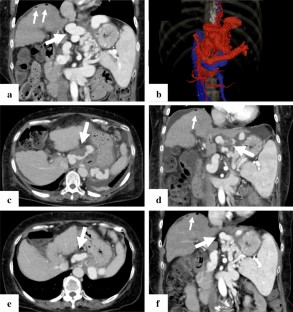

Sofosbuvir/velpatasvir (SOF/VEL) is expected to be highly effective, even in patients with decompensated liver cirrhosis. However, portal hypertension can be problematic after achieving a sustained viral response (SVR), especially in patients with hepatic encephalopathy (HE) associated with large portal-systemic shunt. Although balloon-occluded retrograde transvenous obliteration (BRTO) is a useful option, whether BRTO or SOF/VEL therapy should be initially performed in patients with a poor liver function reserve is controversial. We herein report a case of refractory HE caused by decompensated liver cirrhosis due to hepatitis C virus (HCV) classified as Child–Pugh class C that was treated by BRTO after SVR with SOF/VEL. A 64-year-old woman with HCV-associated decompensated cirrhosis developed refractory HE. Dynamic contrast-enhanced computed tomography (CT) revealed large portal-systemic shunt. We treated the patient with 12 weeks of SOF/VEL, and she achieved SVR. Although the serum albumin level, edema, and ascites were improved, intractable HE remained. Her general condition had been improved after SVR, so HE was suspected to have been caused by portal-systemic shunting. We, therefore, treated the patient by BRTO. On dynamic contrast-enhanced CT, partial obstruction of the shunt vessel was confirmed after BRTO. Thereafter, her serum ammonia level rapidly improved, and HE did not recur. Interventional radiology such as BRTO following SOF/VEL therapy may be a useful option even in patients with decompensated HCV-associated cirrhosis accompanied by portal-systemic shunt.

Fig. 2